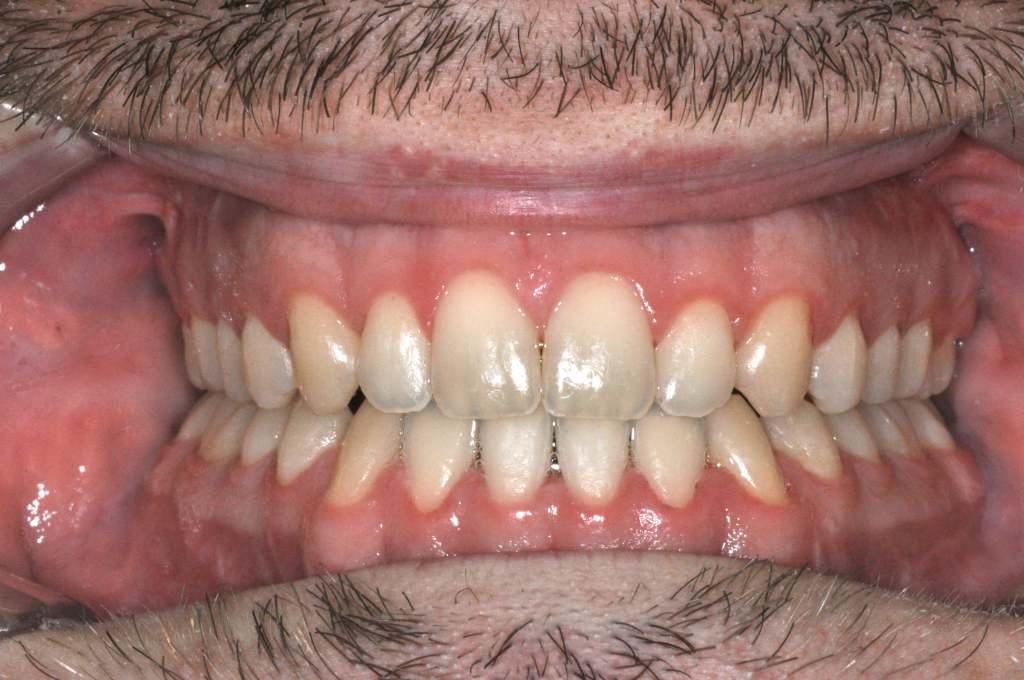

Előtte fogsor - Állcsonti aszimmetria kezelése

Ebben az esetben az arc és a harapás nem egy középvonal mentén működött.

Az alsó állkapocs oldalirányú eltérése instabil harapást és aszimmetrikus mosolyt okozott.

A probléma nem fogállási, hanem állcsonti eredetű volt.

A kezelést fogszabályozással készítettük elő, majd

mindkét állkapocs műtéti áthelyezésével szimmetrizáltuk a harapást és az arc középvonalát.

Eredmény: kiegyensúlyozott harapás, rendezett arcarányok, természetes mosoly.